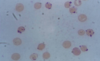

hypochromic, microcytic anemia (since no iron to give shape or color)

anisocytosis (unequal size) and piokilocytosis (tear drop shapped)

- hypochromic, microcytic cells

macrocytic/megloblastic anemia, normochromic

macrocytic, hypersegmented PMN, folate